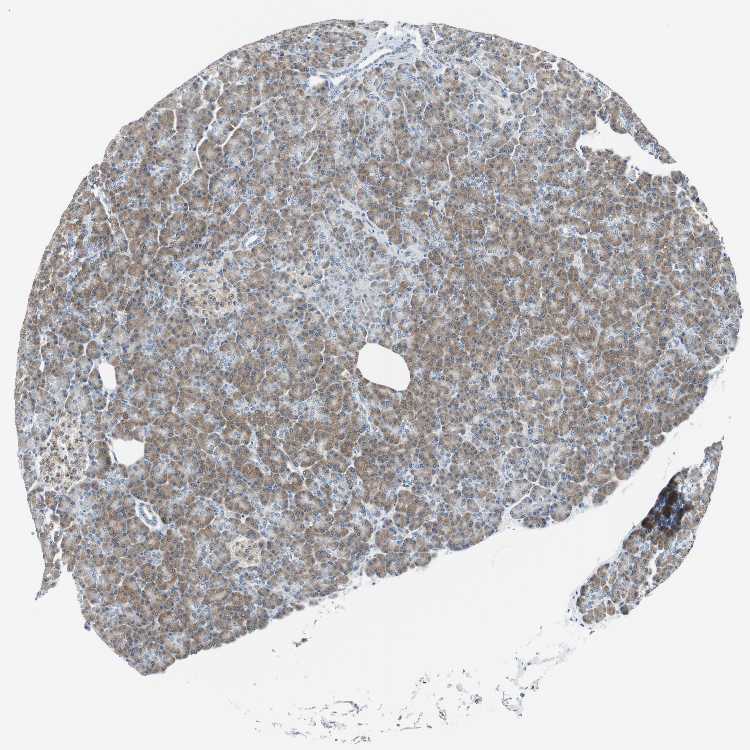

PANCREAS - Antibody stainingi

Antibody staining in the annotated cell types in the current human tissue is reported as not detected, low, medium, or high, based on conventional immunohistochemistry profiling in selected tissues. This score is based on the combination of the staining intensity and fraction of stained cells.

Each image is clickable and will lead to virtual microscopy that enables deeper exploration of all samples and also displays staining intensity scores, fraction scores and subcellular localization as well as patient and tissue information for each sample.

Antibody HPA020994Antibody HPA020996Antibody CAB005035

Exocrine glandular cells LowMediumHigh

Pancreatic endocrine cells MediumMediumLow